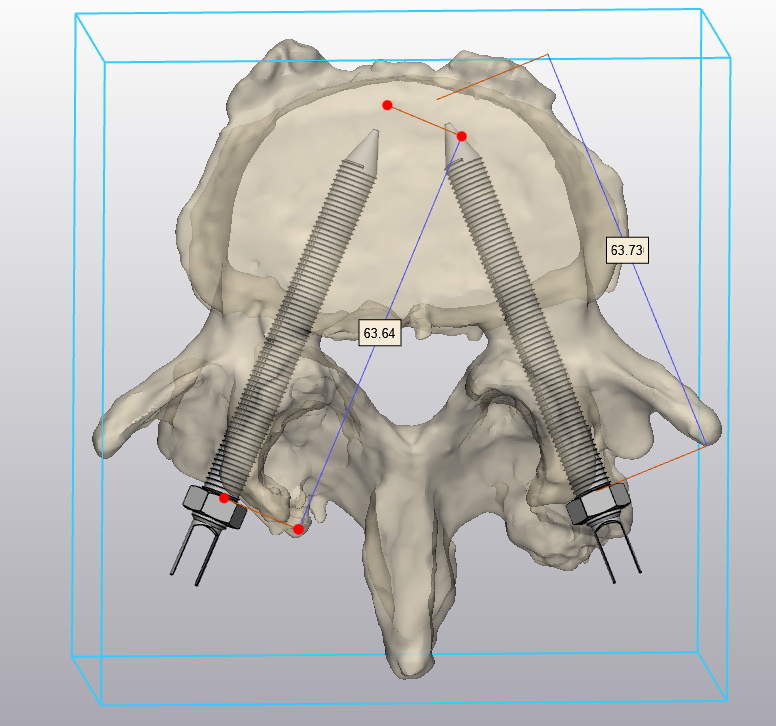

@icsebre 🔊 Èric Barreda: “El model de disseny de peces 3D fa una rèplica exacta de l’anatomia del pacient per poder simular la intervenció quirúrgica que se li realitzarà, prevenint possibles complicacions"

@icsebre 🔎 Aquest model de medicina personalitzada, gràcies a la tecnologia 3D, permet als professionals sanitaris crear pròtesis úniques per a cada pacient, adaptades a les seves necessitats i anatomia, millorant la qualitat de vida.